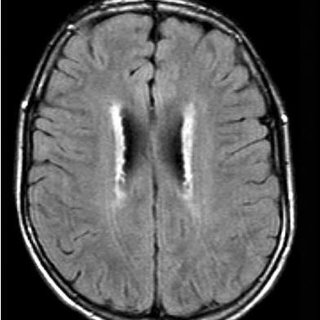

La enfermedad de Alexander, un trastorno progresivo de la sustancia blanca cerebral, se origina debido a una variante patogénica heterocigótica de GFAP (gen que codifica la proteína fibrilar ácida glial). Este trastorno abarca un espectro clínico continuo, mostrando características más definidas y reconocibles en bebés y niños, mientras que en adultos se manifiesta con una variedad de manifestaciones neurológicas más inespecíficas.